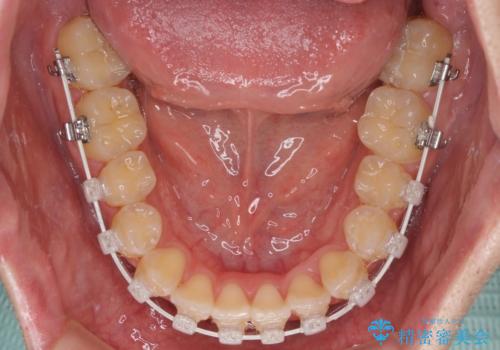

ワイヤー矯正でもマウスピース矯正でも可能でしたが、短期間で、自身の手を煩わせることなく治療を行いたいとのことで、ワイヤー装置にて矯正治療を行うこととしました。

当初予定通り、1年間で治療を終えることができました。